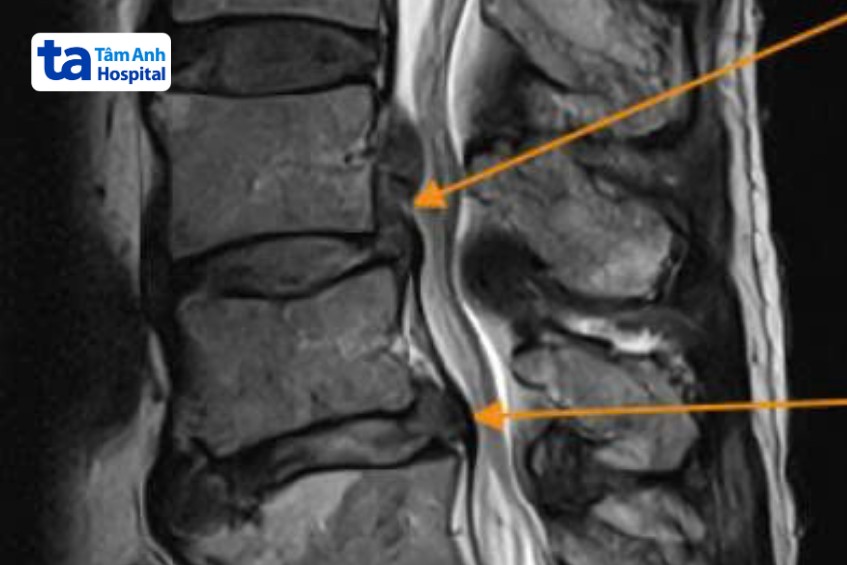

Kết quả chụp MRI và X-quang tại Bệnh viện Đa khoa Tâm Anh TP HCM cho thấy ông Lợi bị thoát vị đĩa đệm vị trí đốt sống lưng L3L4, L4L5, khối thoát vị lớn, chèn ép thần kinh nhiều. Người bệnh cho biết các dấu hiệu đau lưng xuất hiện lần đầu tiên vào khoảng hai năm trước. Ông đi khám, điều trị bảo tồn bằng các loại thuốc đông, tây y. Tuy nhiên, một tuần gần đây, đột ngột đau dữ dội ở vùng lưng, đau lan xuống chân, tiêm thuốc giảm đau không có tác dụng và không thể đi lại hay đứng ngồi như bình thường.